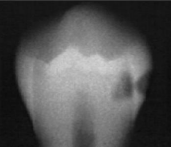

classify this according to radiographic presentation of the ADA

D2

classify this lesion according to the ADA and ICDAS/ICCMS systems

caries within the middle 1/3 of dentin: RB4, D2